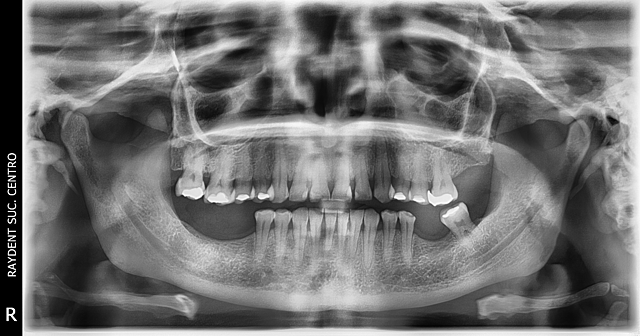

• Análisis Radiográfico.

Análisis Radiográfico.

Se toma radiografía panorámica.